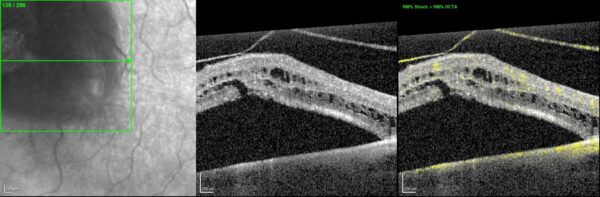

OCT-angiography was inconclusive for the etiological diagnosis (Figure 2).

Figure 2: OCTA macular section scan (Heidelberg Engineering®) of the LE confirming the presence of vitreoretinal traction with subretinal and intraretinal fluid, without any other relevant signs.